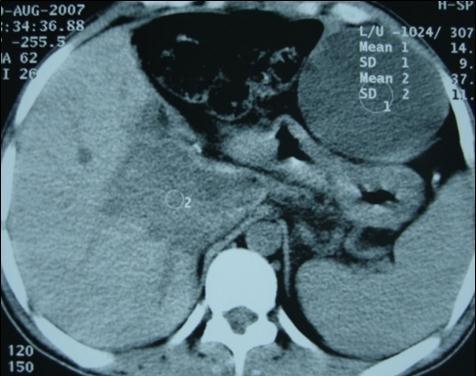

A 27 years-old male patient was admitted with 1 month history of headache, fever, short term memory lack, aphasia, right hemiparesis and seizures. He had liver hydatid cysts excised 8 years before and was treated with adjuvant medication (albendazole). The neurological examination revealed right central third cranial nerve palsy and hemi paresis, with Babinski sign positive, aphasia and papilledema on ocular fundus. The Glasgow Coma Scale was evaluated to 10/15 (E:3; V:1; M:6). A brain CT scan showed a large left temporoparietal intracerebral multiple and calcified hydatid cysts, important mass effect with midline shift about 7 mm following by an obstructive hydrocephalus (Figure 1). Other cysts were found in thalamic region (Figure 2). The Thoraco-abdominal CT scan showed multiple intra peritoneal hydatid cysts (Figure 3). A left temporo parietal craniotomy was performed in emergency. After corticectomy, using Arana-Iniguez technique, the appearance of the capsule suggested infected hydatid cysts with a purulent material which was aspirated. Numerous hydatid cysts were lifted away and several daughter vesicles were carefully removed without rupture (Figure 4). Macroscopically, the abscess wall appeared to be thick, calcified and tightly attached to lateral ventricular, so it could not be removed. The deep cyst overlying the third ventricle was left.in place. Microscopic examination demonstrated live scoleces, protoscoleces and multiple hooks. These findings are consistent with hydatid cyst (granulosis ecchinococcus) (Figure 5). Bacteriology examination found several white blood cells in the pus (neutrophilia) and infection by streptococcus pneumonia. This was consistent with infection. After surgery, the patient had medication (albendazole, specific antibiotherapy and phenobarbital). The inflammation assessment in the blood showed leukocytosis, a high C-reactive protein rate and increased erythrocyte sedimentation rate. Post operative CT scan was performed and showed the residual calcified capsule and decreased ventricular size (Figure 6). Clinical improvement was achieved after treatment. One month after the initial diagnosis, CT scan of the brain showed no recurrence and a physical examination revealed a neurologically intact, fully functional patient and eyes fundus normal. He was discharged and went to abdominal surgery two months later with complete intra abdominal cysts removal. Albendazole treatment was continuing for six months and radiological exploration was performed by brain MRI with spectroscopy at three and six month later. This showed that infection had resolved and the deep cyst overlying the third ventricle is less spherical (Figure 7, Figure 8). Four years later, the outcome was good.

Figure 3.Abdominal CT scan showing intraperitoneal hydatid cysts